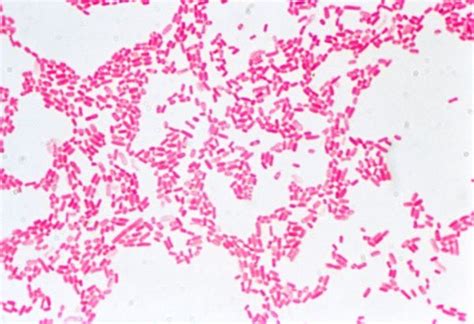

8. Microscopic Examination: Observe the slide under a microscope to determine the Gram reaction of the bacteria. Gram-positive bacteria will appear purple or blue, while Gram-negative bacteria will appear pink or red.

• Gram-Negative Bacteria: These bacteria lose the crystal violet stain during the decolorization step and take up the counterstain, appearing pink or red. Examples include *Escherichia coli* (*E. coli*) and *Pseudomonas*.